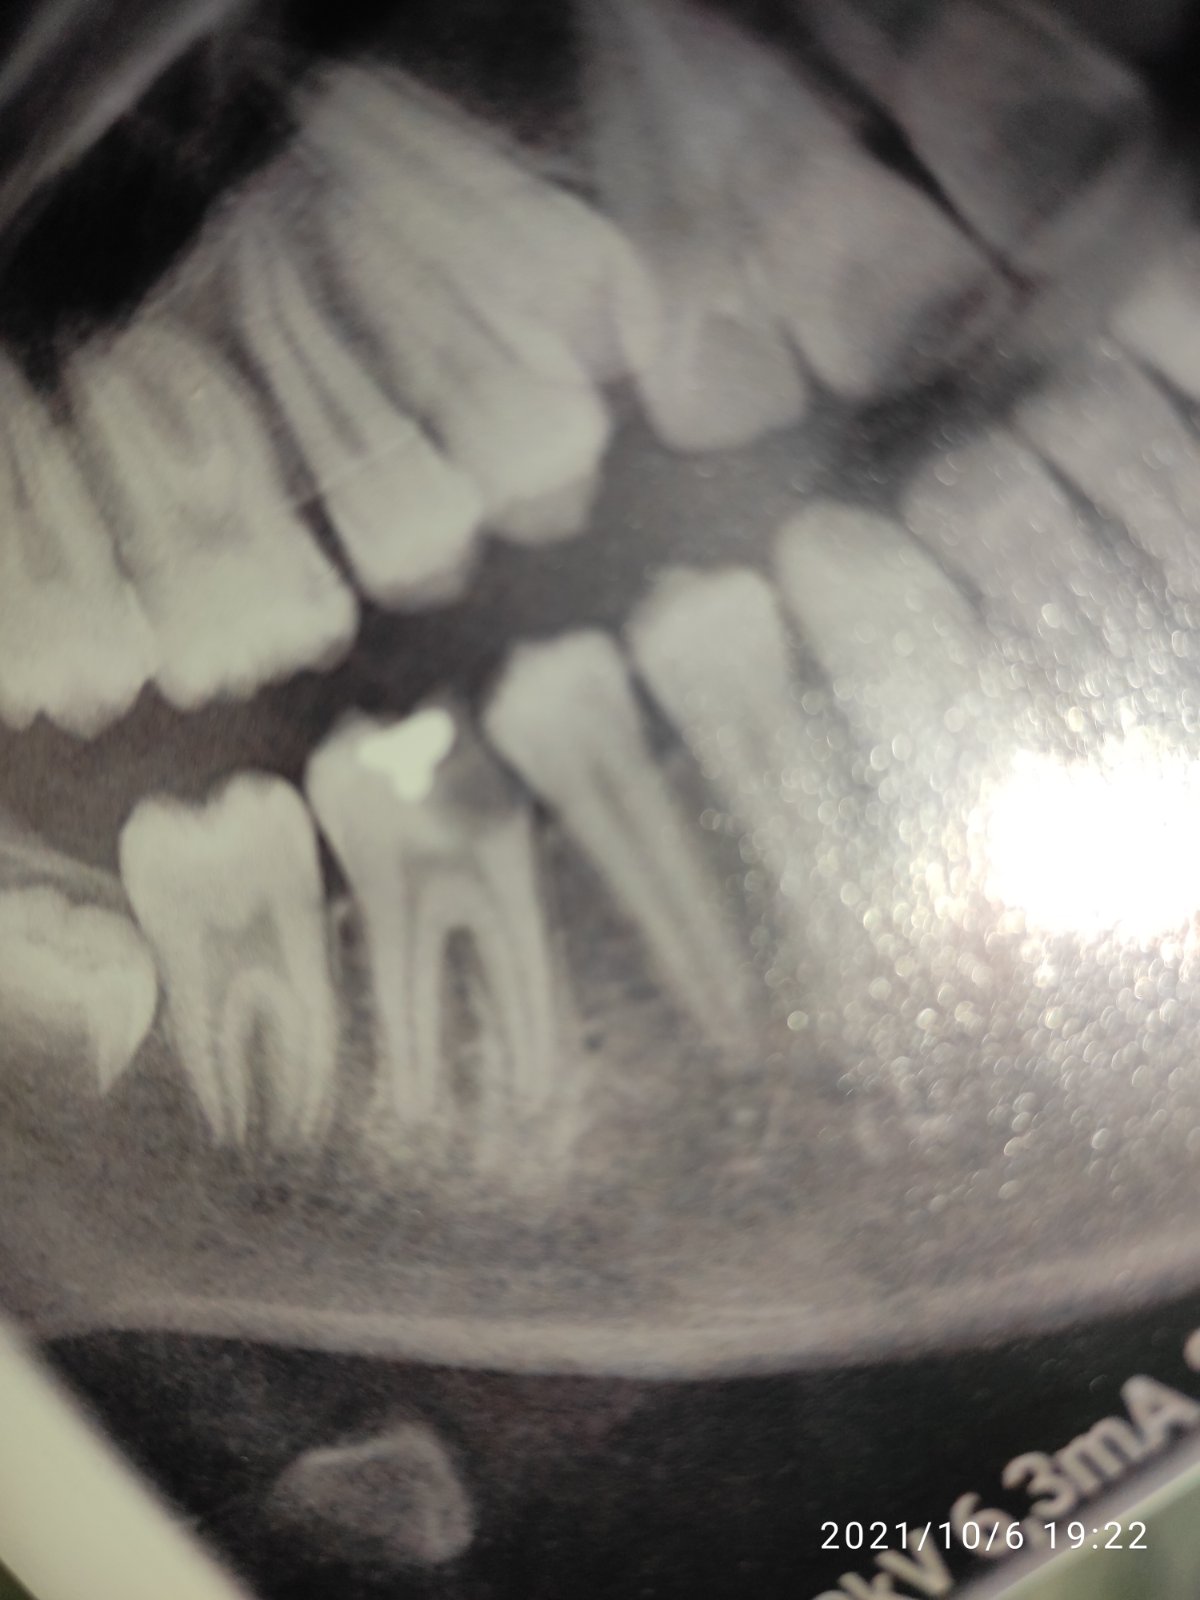

Záleží ako znášate bolesť. Kaz je blízko drene. Je možné, že odstraňovaním kazu sa otvorí kanálik a ten radšej s injekciou.

@eeellllllaaaaa Urcite anestezu. Kaz je hlboky a pravdepodobne bude treba devitalizovat zub.

@eeellllllaaaaa kaz je rozsiahly, dosť hlboký a blízko zub drene, ja by som si pýtala anestéziu.